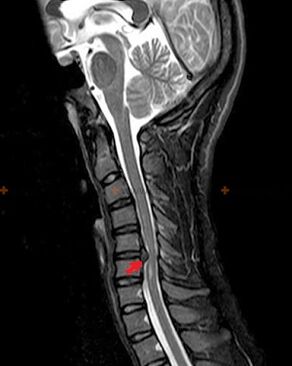

Lai diagnosticētu osteohondrozi, tiek izmantotas šādas izpētes metodes: radiogrāfija (vēlams ar funkcionāliem testiem), MSCT un MRI. Pēdējais pētījums ir vispiemērotākais, jo tas ļauj ļoti skaidri vizualizēt starpskriemeļu struktūru stāvokli.

Iepriekš aprakstīto izmaiņu klātbūtne, kā arī starpskriemeļu diska struktūras izmaiņas, kas konstatētas ar MSCT un MRI, kalpo kā uzticamas pazīmes, kas apstiprina osteohondrozes klātbūtni.